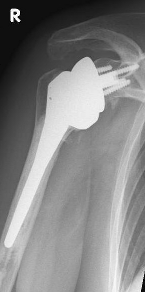

Right: radiograph of an inverse shoulder prosthesis for rotator cuff defect arthropathy.

left: Inverted shoulder prosthesis (Aequalis reversed type, Tornier company).